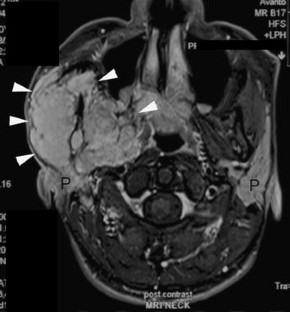

A Rare Case of Basal Cell Adenocarcinoma of Parotid Gland with Intracranial Extension

Basal cell adenocarcinoma (BCAC) is a rare tumour entity. Despite its tendency to be infiltrative and destructive tumour with propensity to recur, it rarely metastasizes and long-term outcome following surgery is favourable. This paper presents a 42-year-old male with residual BCAC of parotid gland that had extended into infratemporal fossa and intracranial. The important aspect of this case is the rarity occurrence of BCAC of parotid with intracranial extension and its surgical approaches to achieve tumour clearance.

Fig. 1